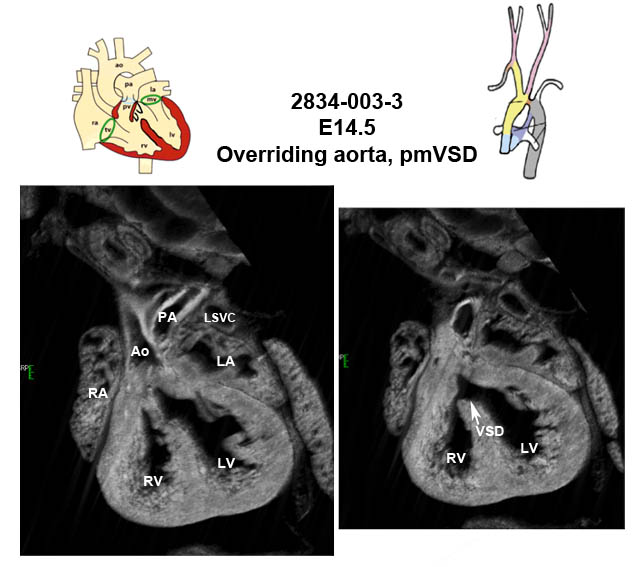

Caption EFIC Summary

Copyright This image is from the Laboratory of Dr. Cecilia Lo, a member of the Cardiovascular Development Consortium (CvDC), Bench to Bassinet (B2B) program of the National Heart Lung and Blood Institute (NHLBI), and is displayed with the permission of the authors. J:175213

Zfp366b2b2834Clo zinc finger protein 366; Bench to Bassinet Program (B2B/CVDC), mutation 2834 Cecilia Lo

Zfp366b2b2834Clo/Zfp366b2b2834Clo C57BL/6J-Zfp366b2b2834Clo